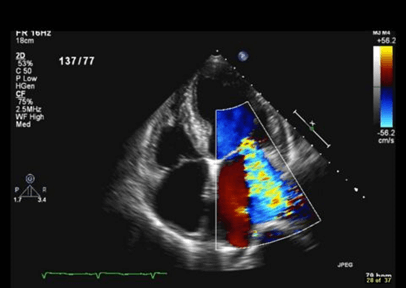

– Siêu âm Doppler

Bằng sóng siêu âm, bác sĩ có thể quan sát được cấu trúc tim; cách tim hoạt động, co bóp; kích thước tim, hình dạng tim; kích thước và chuyển động của các thành tim; sự hoạt động của van tim,…

-Bệnh lý về van tim: Hẹp van tim, hở van tim,… Đây là loại bệnh xảy ra khi cấu trúc của các lá van bị biến dạng, van tim không đóng kín, máu lưu thông ngược trở lại buồng tim.